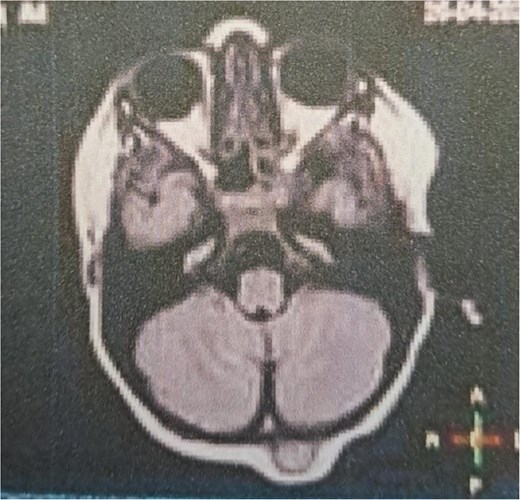

A 4-year-old, otherwise healthy male with no significant past medical history, family history of bone disorders, or prior trauma, presented with a progressively enlarging, painless occipital swelling noticed by his parents over a two-month period. The parents denied any associated symptoms, including fever, headache, vomiting, changes in behavior, or neurological deficits such as visual disturbances or gait abnormalities. There was no history of recent infections or constitutional symptoms. On physical examination, the child was afebrile and hemodynamically stable. A solitary, well-circumscribed, firm, non-mobile, and non-tender mass measuring 1.5 × 1.5 cm was palpated in the midline occipital region. The overlying skin was normal in color and temperature, with no erythema, ulceration, or punctum. No regional lymphadenopathy was detected. Neurological examination, including cranial nerve assessment, motor/sensory function, and reflexes, was unremarkable. Brain computed tomography (CT) with contrast revealed a 14 × 12 mm, well-defined, osteolytic, interosseous lesion in the occipital bone, exhibiting smooth sclerotic margins, cortical thinning, and no periosteal reaction or internal matrix mineralization, the lesion was confined to the diploic space, sparing the inner and outer cortical tables, with no intracranial extension or dural involvement (Figs 1 and 2). Magnetic resonance imaging (MRI) without contrast enhancement, T1-weighted imaging (T1WI) showed an extra-axial space-occupying mass, the mass is iso-intense and well-circumscribed in shape (Fig. 3).

MRI T1WI axial view without contrast enhancement showing an extra-axial space-occupying mass, iso-intense and well-circumscribed in shape.